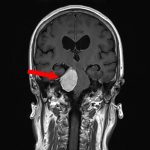

手術前1